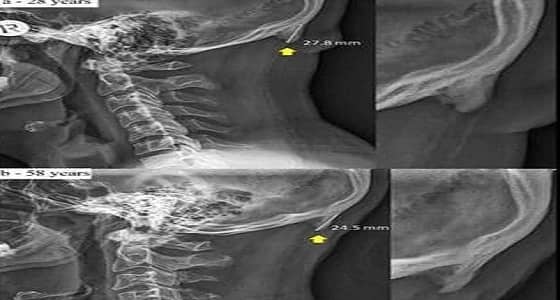

كشف خبراء أستراليين أن الشخص الذي يكثر من استخدام الهاتف الذكي، يظهر لديه ما يشبه شوكة عظمية في الجهة الخلفية من جمجمة الرأس، بسبب الانحناء والتركيز في شاشة الجهاز.

وقالت الدراسة التي جرى إعدادها في جامعة " سان شان كوست " الأسترالية، أن جمجمة الإنسان أضحت تحدث هذه " الشوكة العظمية " بشكل متزايد.

وأضافت: تبرز هذه الشوكة العظمية بشكل أسرع لدى الشباب الذين تتراوح أعمارهم بين 18 و30 سنة، واعتمدت الدراسة على عينة من ألف جمجمة.